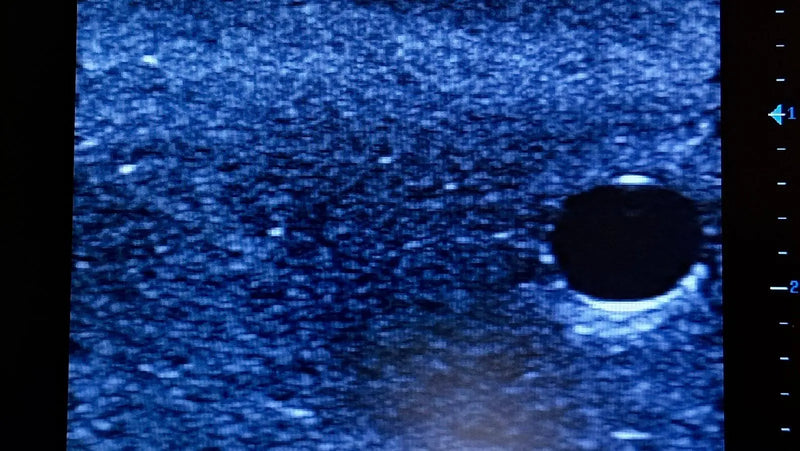

Thiết bị huấn luyện đơn giản, mạnh mẽ cho phép luyện tập lặp đi lặp lại kỹ thuật xâm nhập dưới hướng dẫn siêu âm một cách thực tế, giúp nâng cao thành thạo máy siêu âm, khéo léo sử dụng đầu dò và nhận biết cấu trúc giải phẫu. Tất cả chỉ với việc chuẩn bị và bảo trì tối thiểu.

Máy huấn luyện siêu âm BIOTME® mô phỏng mô người thật cả về cảm giác và đặc tính phản hồi sóng siêu âm. Vết kim sẽ biến mất sau vài ngày luyện tập, tăng cường tính chân thực và tiết kiệm chi phí.

Kích thước (Inch): 13 x 6.7 x 3.15